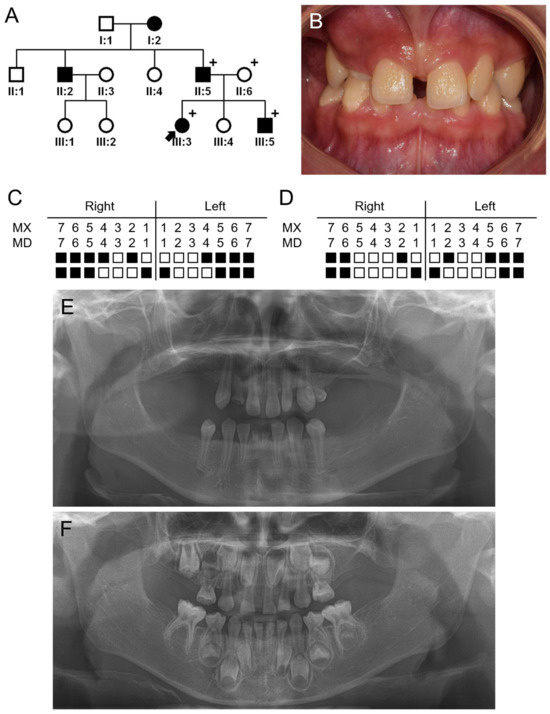

3.2. Family 2